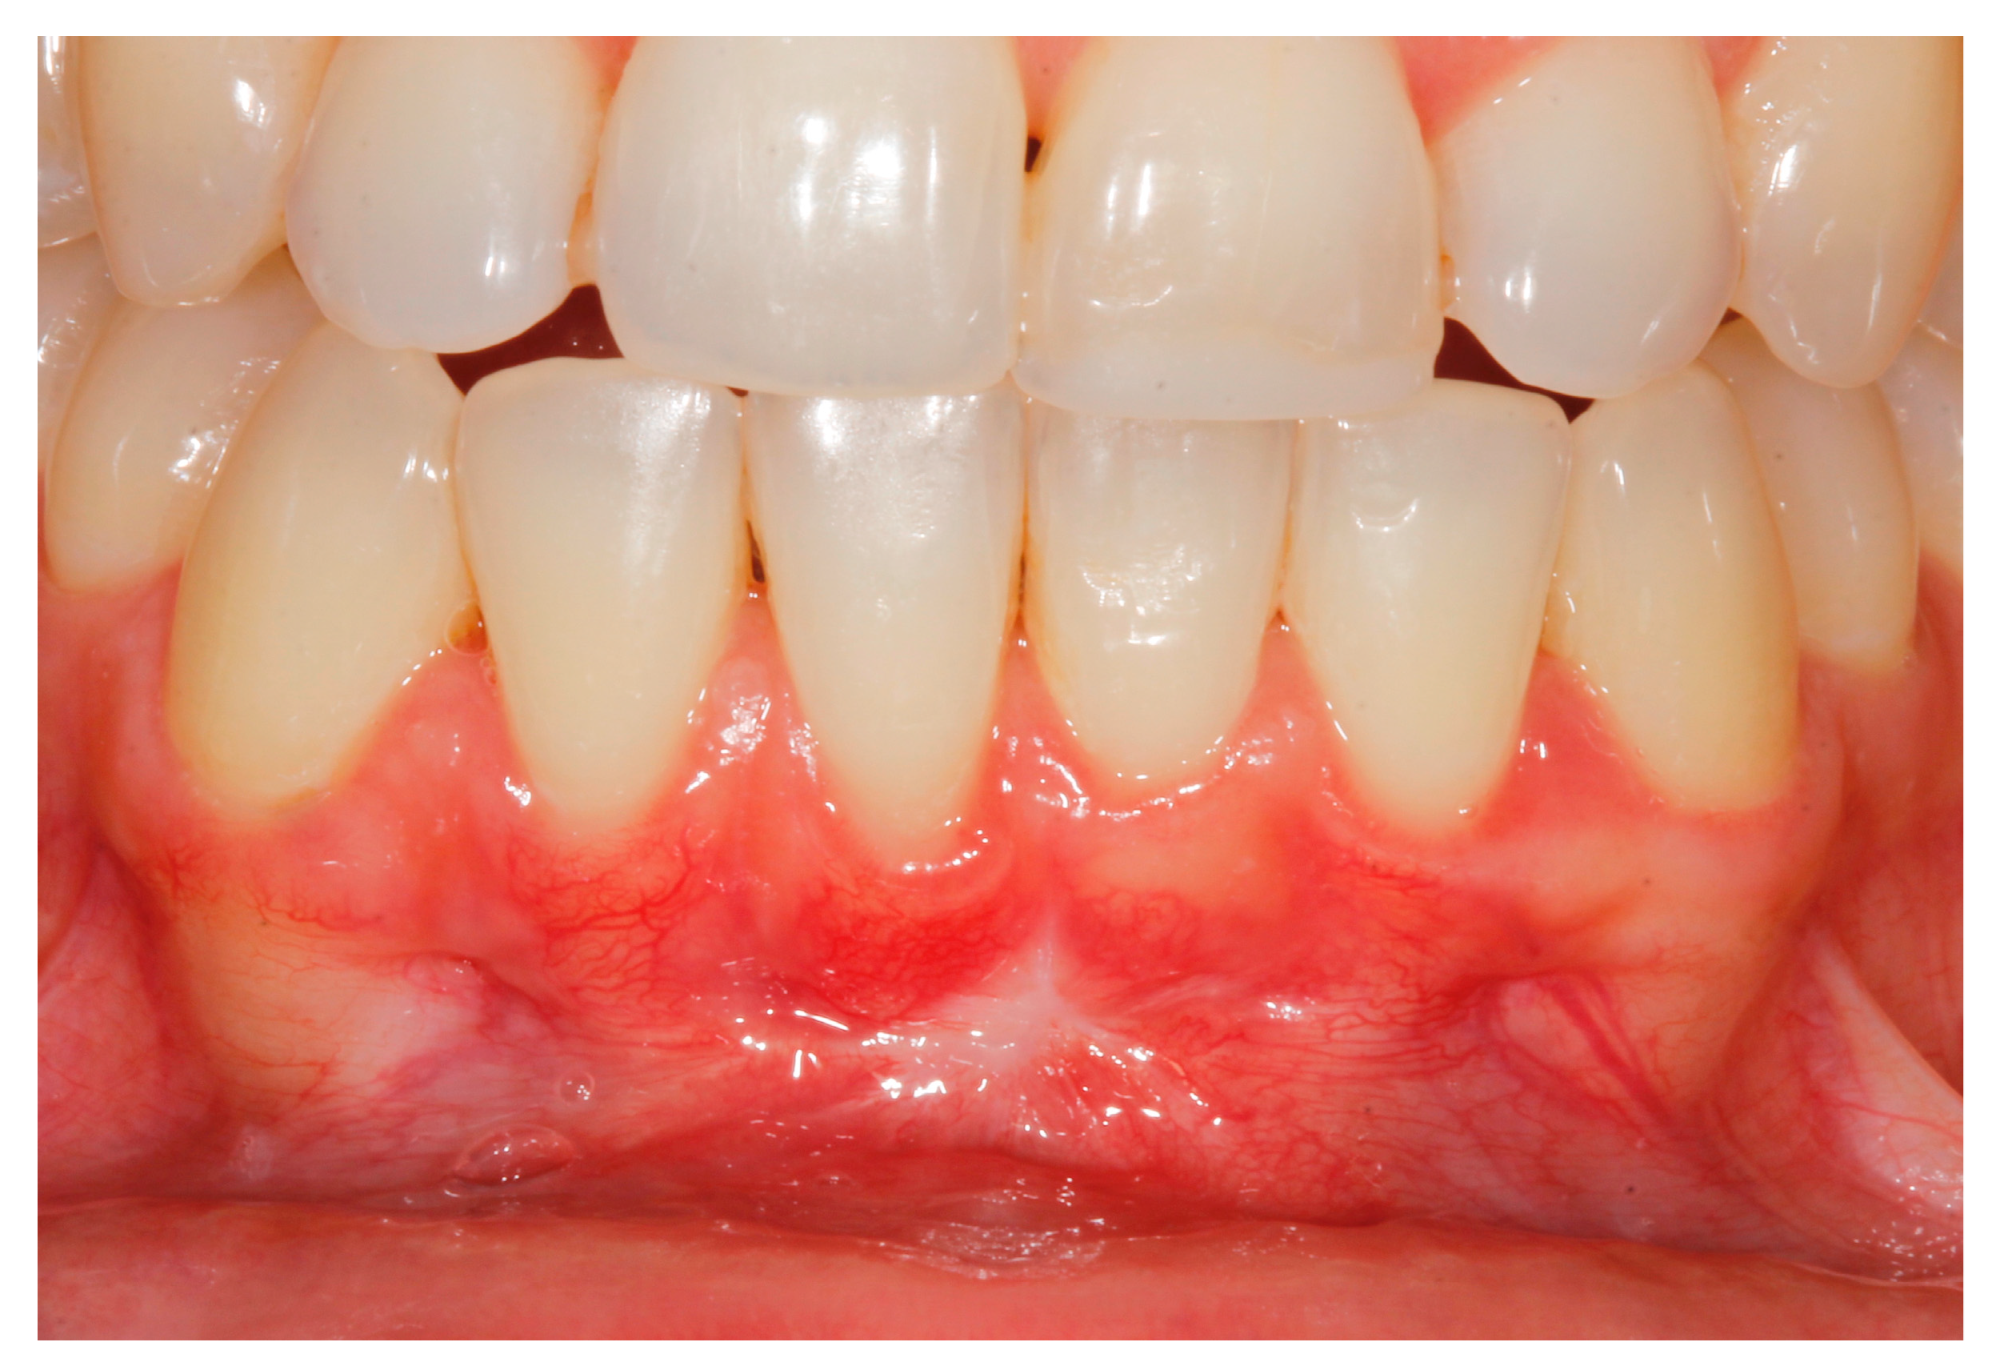

2. Case Study